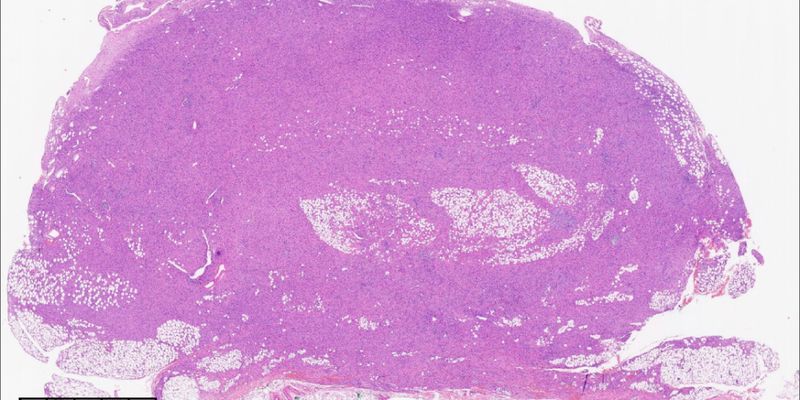

深入了解NTRK重排的梭形细胞肿瘤病例,探讨其病理特征、分子诊断及靶向治疗进展。文章详细解析NTRK基因融合的诊断意义,并介绍拉罗替尼、恩曲替尼、瑞普替尼等TRK抑制剂在治疗中的应用,为患者提供前沿用药信息及海外购药指导。 Read More... "NTRK重排梭形细胞肿瘤:罕见病例解析与靶向治疗新希望"